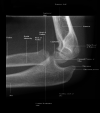

Models for diagnostic reasoning in radiology have been based on the observed behaviors of experienced radiologists but have not directly focused on the thought processes of novices as they improve their accuracy of image interpretation. By collecting think-aloud verbal reports, the current study was designed to investigate differences in specific thought processes between medical students (novices) as they learn and radiologists (experts), so that we can better design future instructional environments. Seven medical students and four physicians with radiology training were asked to interpret and diagnose pediatric elbow radiographs where fracture is suspected. After reporting their diagnosis of a case, they were given immediate feedback. Participants were asked to verbalize their thoughts while completing the diagnosis and while they reflected on the provided feedback. The protocol analysis of their verbalizations showed that participants used some combination of four processes to interpret the case: gestalt interpretation, purposeful search, rule application, and reasoning from a prior case. All types of processes except reasoning from a prior case were applied significantly more frequently by experts. Further, gestalt interpretation was used with higher frequency in abnormal cases while purposeful search was used more often for normal cases. Our assessment of processes could help guide the design of instructional environments with well-curated image banks and analytics to facilitate the novice's journey to expertise in image interpretation.